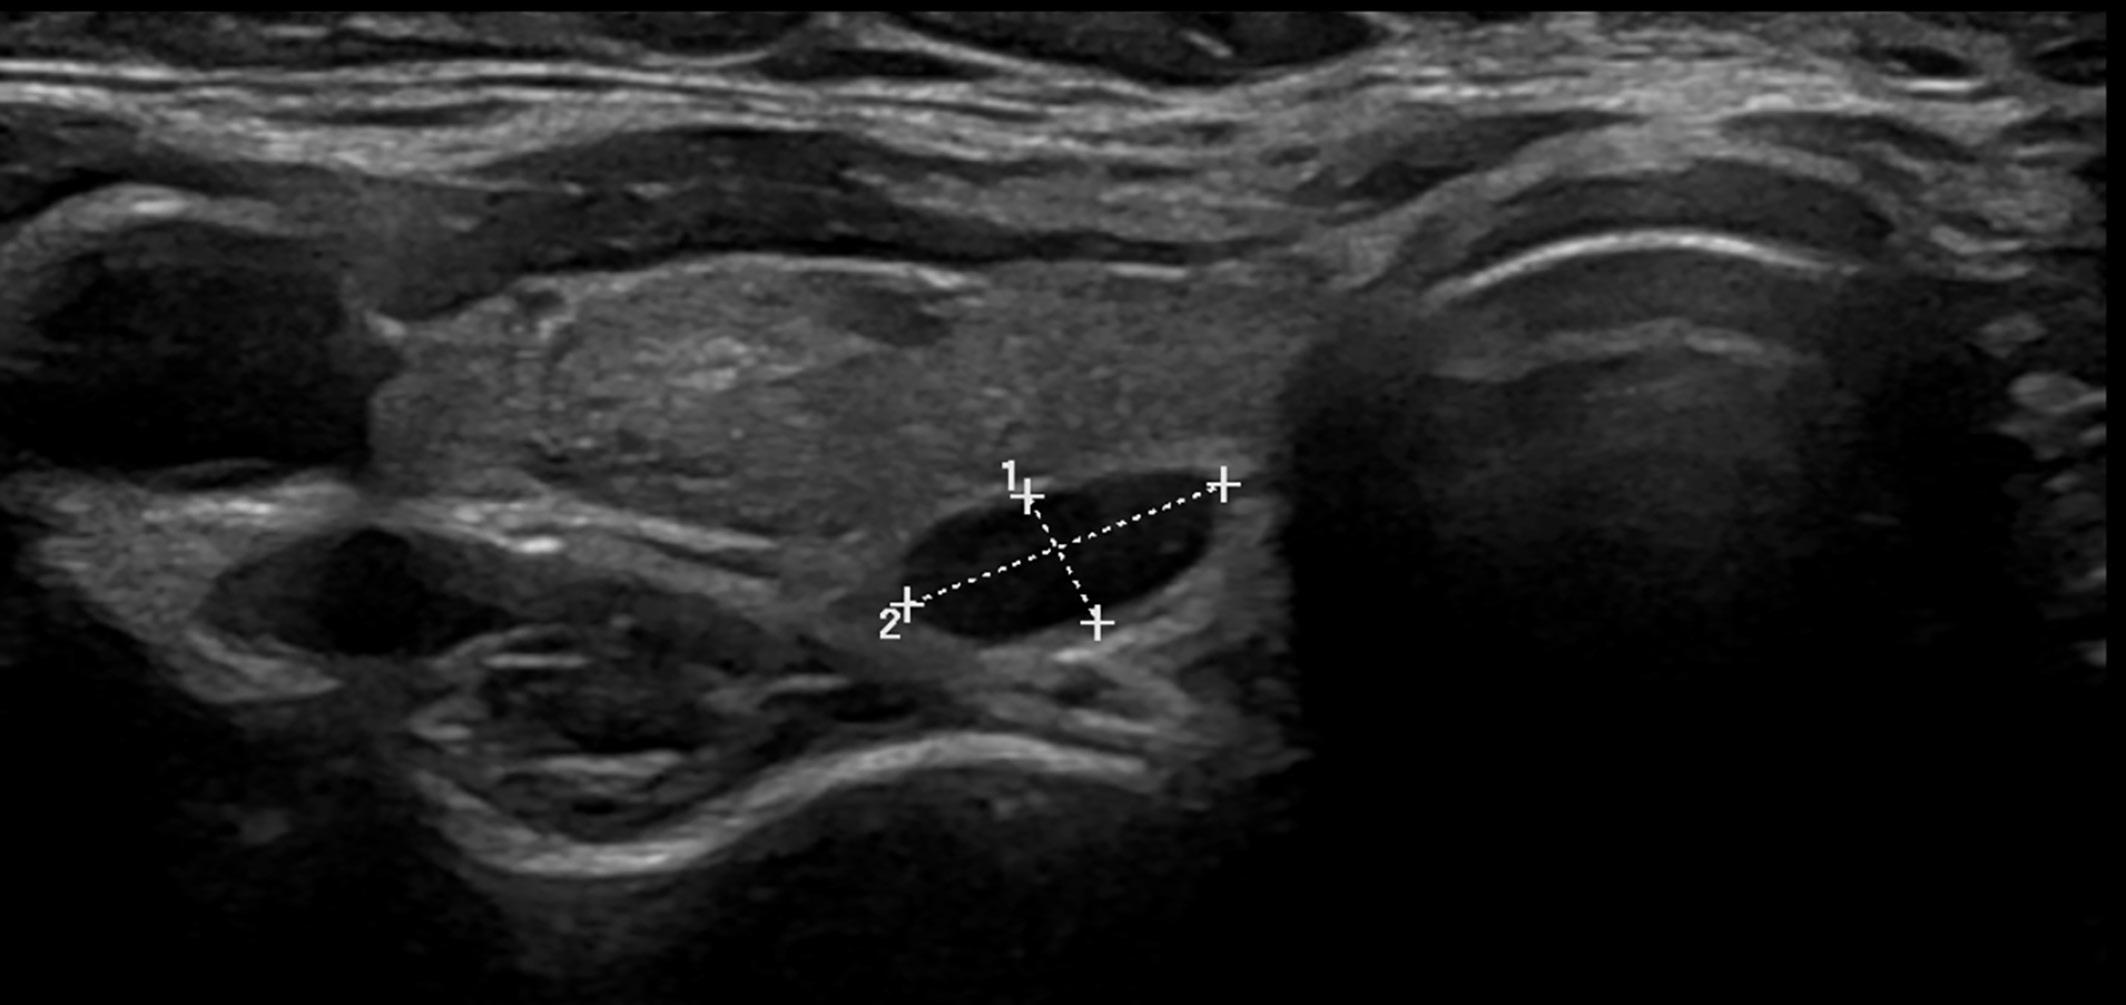

Markering av ikke-palpable maligne og pre-maligne tumores i brystet med metalltråd har vært avgjørende for innføringen av brystbevarende kirurgi. Palpable svulster må nå i tillegg markeres hos pasienter som får neoadjuvant behandling. Ny teknologi er i ferd med å erstatte tradisjonell trådmarkering i stor grad, og kan gi både bedre logistikk og bedre behandlingsresultater. I artikkelen beskriver vi de mest aktuelle markeringssystemene til bruk i klinikken.

Tradisjonell trådmarkering av små brystlesjoner ble utviklet i 1979 av Ferris Hall og Howard Frank (1). De oppfant en metalltråd med krok som kunne plasseres i brystet ved radiologisk veiledning for å muliggjøre lokalisering av ikke-palpable lesjoner under operasjonen. Metoden var avgjørende for utviklingen av brystbevarende kirurgi for brystkreft i påfølgende tiår. Trådmarkering er særlig aktuell ved fjerning av små, screening-detekterte lesjoner. Den har flere fordeler, blant annet enkel plassering i brystet ved hjelp av ultralyd eller stereotaktisk veiledning. Metoden er godt utprøvd, og tråden kan enkelt plasseres på nytt dersom den blir feilplassert.

Ulempene med trådmarkering inkluderer forsinkelser i operasjonen på grunn av preoperativ lokalisering og kirurgisk planlegging, plagsomme, utstikkende tråder fra brystet ved desinfisering og kirurgi, risiko for forskyvning av tråden før og under operasjonen, samt begrensninger i valg av snittsted på grunn av tråden(e)s plassering. Pasienter opplever ofte tråden som ubehagelig, og den kan føre til stress og bekymring for at den skal forskyves før operasjonen (2,3) Derfor er tradisjonell markering blitt utfordret særlig det siste tiåret av flere nye, «trådløse» alternativer (4,5). De nye metodene benytter markører på størrelse med et riskorn og kan plasseres i lesjonen flere uker eller måneder før operasjonen, noe som forenkler logistikk og tillater plassering før neoadjuvant behandling.

MAGNETISK KORN

På samme måte som radioaktive jodkorn kan et magnetisk korn plasseres i brystlesjonen ved hjelp av ultralyd eller stereotaktisk veiledning. Magnetiske korn kan enkelt identifiseres med en magnetisk detektor under kirurgien. Sentimag® er en del av et system som inkluderer både detektoren og det magnetiske kornet, kalt Magseed®. Sirius Pintuition er en annen leverandør (6). Den mest omdiskuterte ulempen ved bruk av magnetiske korn er artefaktene de skaper på MR-bilder av brystet, da de er laget av stål. Kornet forstyrrer magnetfeltene, og bør derfor bare legges inn når utredning med MR og eventuelt oppfølgning av neoadjuvant behandling er ferdig. Dette gjør at den logistiske fordelen med metoden blir noe mindre enn hos konkurrentene, spesielt hos pasienter som gjennomgår neoadjuvant behandling.

RADAR- OG RADIOFREKVENS - SYSTEM

SCOUT®-systemet (Merit Medical, Utah, USA) bruker en liten elektromagnetisk radarreflektor som plasseres i brystlesjonen ved hjelp av ultralyd- eller stereotaktisk veiledning. Fordelen med teknologien er at markøren skaper lite artefakt på MR. Dermed er det uproblematisk å legge den inn på diagnosetidspunktet og før man vet om det skal tas MR senere i utredningen eller som respons-

evaluering. Under operasjonen aktiveres reflektoren av infrarøde lysimpulser generert av en konsollprobe og reflekterer et elektromagnetisk bølgesignal tilbake til håndstykket (Figur 1).

LOCalizer® er leverandør av markeringssystem som bruker radiofrekvens-identifikasjon (RFID)-brikker bygd inn i små markør-kapsler som deponeres i brystet på tilsvarende måte som de øvrige omtalte markørene. Systemet som brukes på operasjonsstuen er trådløst og noe mer kompakt enn hos de andre leverandørene. Teknologien er den samme som brukes i bankkort blant annet. Markørene gir større artefakt på MR enn radarreflektorene, men ikke så mye som stål-korn. I likhet med stålkorn og radar-reflektorer er det ingen tidsbegrensning i hvor lenge de kan ligge i kroppen før kirurgi.

ERFARINGER FRA INNFØRING AV SCOUT®- SYSTEMET

VED UNIVERSITETSSYKEHUSET NORD - NORGE TROMSØ SCOUT®-systemet ble innført som rutine ved Universitetssykehuset Nord-Norge i 2020 og har i stor grad erstattet trådmarkering. Selv om markørene koster mer enn merketråd har dette forenklet logistikken og redusert kostnadene betydelig da vi sparer besøk hos radiolog for markering i forbindelse med operasjonen. Det er også en fordel for planleggingen at operasjonen frikobles fra innleggelse av markering. De fleste pasientene får markør innlagt ved diagnosetidspunktet, altså uker eller måneder

før operasjonen. En fersk studie viser at karbonavtrykket i forbindelse med markering er betydelig lavere enn ved tradisjonell trådmarkering (7). De totale kostnadene for samfunnet er antagelig også lavere på grunn av den forenklede logistikken, og raskere operasjonstid, dog er dette et komplisert regnestykke. Våre resultater fra de første 100 pasientene etter innføring av SCOUT® viste redusert tidsbruk på operasjonsstua med ca. 20 minutter per pasient (8). Enda større betydning har det at bruk av både SCOUT®-markering og markering med radioaktive jodkorn ser ut til å redusere andelen pasienter som får ufrie marginer og behov for reoperasjon (8,9). I vårt materiale ble antallet ufrie marginer og reoperasjoner halvert. Studier som sammenligner overlevelse ved de ulike metoder mangler.

SCOUT®-markering har ikke erstattet tradisjonell trådmarkering fullstendig ved Universitetssykehuset Nord-Norge. Hos pasienter med multiple lesjoner eller store premaligne forandringer kreves ofte flere markeringspunkter i brystet. I disse tilfellene kan det være gunstig å kombinere trådmarkering og SCOUT®-markør.

Bruker man to eller flere SCOUT®-markører bør disse ligge minst 4 cm fra hverandre for å kunne identifiseres separat.

Figur 1, 2 og 3 viser hhv SCOUT®-systemets konsollprobe, SCOUT®-systemets 16G nåler, samt preparatmammografi med reflektor plassert sentralt. Alle bilder tatt ved vår klinikk.

KONKLUSJON

Tradisjonell trådmarkering bør erstattes med ny teknologi. Gevinsten er bedre logistikk, lavere karbonavtrykk og færre reoperasjoner. Markering av lesjoner i både bryst og aksille før neoadjuvant behandling er aktuelt for en stadig større andel av brystkreftpasientene. Ved valg av metode bør lokale logistiske forhold veie tungt, og man bør ta særlig hensyn til de neoadjuvante behandlingsforløpene i dette valget.